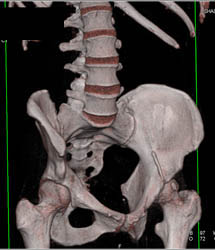

Dislocated Left Hip Prosthesis